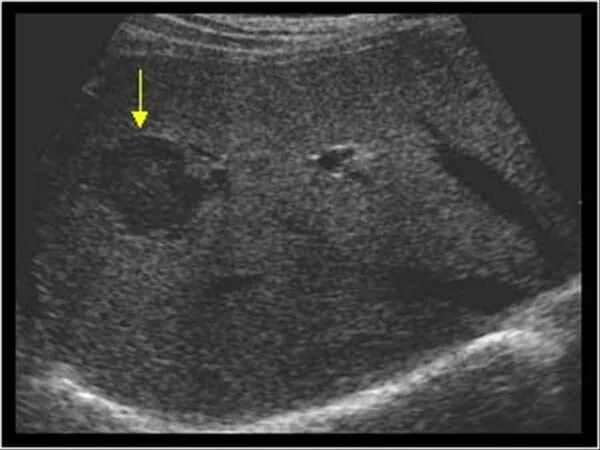

Метастазы в печени на узи как выглядят